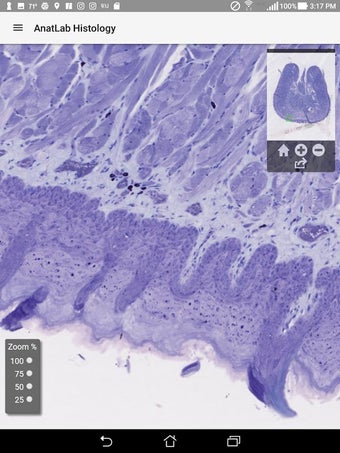

AnatLab Histology es una aplicación gratuita para Android desarrollada por Eolas Technologies Inc. que proporciona a los usuarios imágenes de diapositivas microscópicas de ultra alta resolución. Esta aplicación es una herramienta ideal para estudiantes, profesores, investigadores y el público en general. Con esta aplicación, pueden explorar el paisaje microscópico completo del cuerpo como si estuvieran mirando una colección de diapositivas reales en un microscopio físico. Tiene una función basada en la nube, la aplicación se puede acceder en cualquier dispositivo móvil Android, lo que la hace muy conveniente y accesible.

La aplicación ofrece una colección completa de imágenes de diapositivas microscópicas de histología que se pueden ver en ultra alta resolución. Las imágenes son de calidad excepcional y proporcionan una representación precisa del paisaje microscópico del cuerpo. La aplicación es fácil de usar y navegar, lo que permite a los usuarios explorar diferentes partes del cuerpo con facilidad.